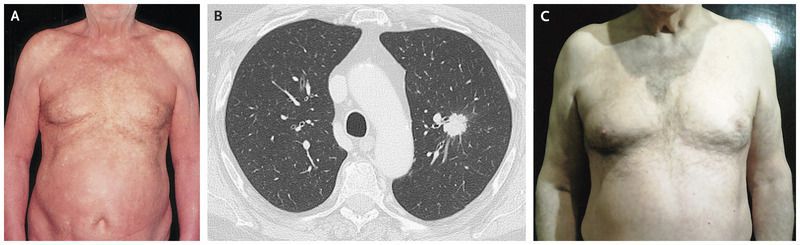

A 73-year-old man presented to the dermatology clinic with a persistent, generalized rash that had been present for 3 months and was associated with occasional itching. He had no history of any previous dermatoses or drug allergies; he was an active smoker, with a smoking history of 40 pack-years. Physical examination revealed a symmetric, generalized erythematous rash (Panel A), with overlying scaling and desquamation involving the hands and feet. He was initially treated with topical glucocorticoid therapy, then with oral prednisone and antihistamines, and then with intravenous glucocorticoids, but had no relief. Skin biopsy revealed a slight acanthosis and parakeratosis with a granulocytic infiltrate — findings that were consistent with an erythrodermic dermatitis. Given the patient’s smoking history and concern that there was an underlying neoplasm associated with the dermatitis, a radiograph of the chest was obtained, which showed an opacity in the left lung. Paraneoplastic erythroderma was suspected, and computed tomography of the chest confirmed the presence of a pulmonary nodule in the left upper lobe (Panel B). The patient underwent upper lobectomy of the left lung and lymph node dissection. Histologic examination revealed a moderately differentiated squamous-cell carcinoma. Paraneoplastic erythroderma is an uncommon initial manifestation of lung cancer. It can also be associated with hematologic cancers and other solid-organ cancers. One month after resection, the patient had complete resolution of the rash (Panel C). One year later, he had no further rash or tumor recurrence.